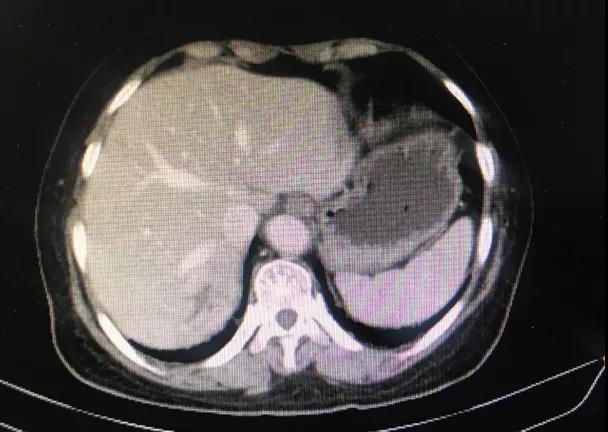

乳腺超声:右乳1-2点乳晕处探及低回声,大小约3.5 cm x 1.6 cm。肝脏超声:肝内转移瘤,最大位于肝右后叶,约5.0 cm x 3.8 cm。胸腹部CT:右乳内上象限结节,大小约2.0 cm x 1.8 cm,分叶状,边缘多发毛刺,考虑恶性。双肺多发结节,大者约0.5 cm x 0.5 cm,考虑转移。肝脏内多发结节,大者约4.5 cm x 3.9 cm,考虑转移。PET-CT检查:右乳恶性结节,约1.9 cm x 1.7 cm,双肺多发转移结节,大者约0.6 cm x 0.5 cm,肝脏多发转移结节,大者约5.0 cm x 4.6 cm。

一线内分泌治疗进展后,换用化疗。于2019年7月至2020年5月期间接受口服长春瑞滨单药50mg 每周三次治疗,共用药11个月。毒副作用评估,表现为Ⅰ度骨髓抑制。疗效评价:最佳疗效SD,PFS 11个月;CT评估:乳腺病灶2.6 cm → 2.7 cm → 3.5 cm;肺转移灶0.7 cm → 0.7 cm → 1.3 cm;肝转移灶4.0 cm → 3.1 cm → 4.5 cm。